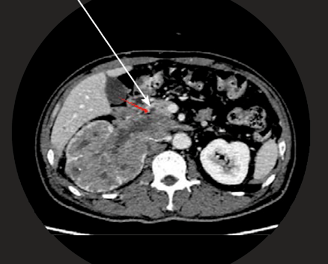

The AIVR.4D Robotics System successfully detected cancer thrombi and tumor invasion along the wall of the Inferior Vena Cava (IVC)—a complex and often overlooked diagnostic challenge with conventional 2D CT imaging.

AIVR.4D pinpoints critical invasion sites—such as tumor spread along the Inferior Vena Cava (IVC)—by highlighting organs, vessels, and tumors with 98% clarity.